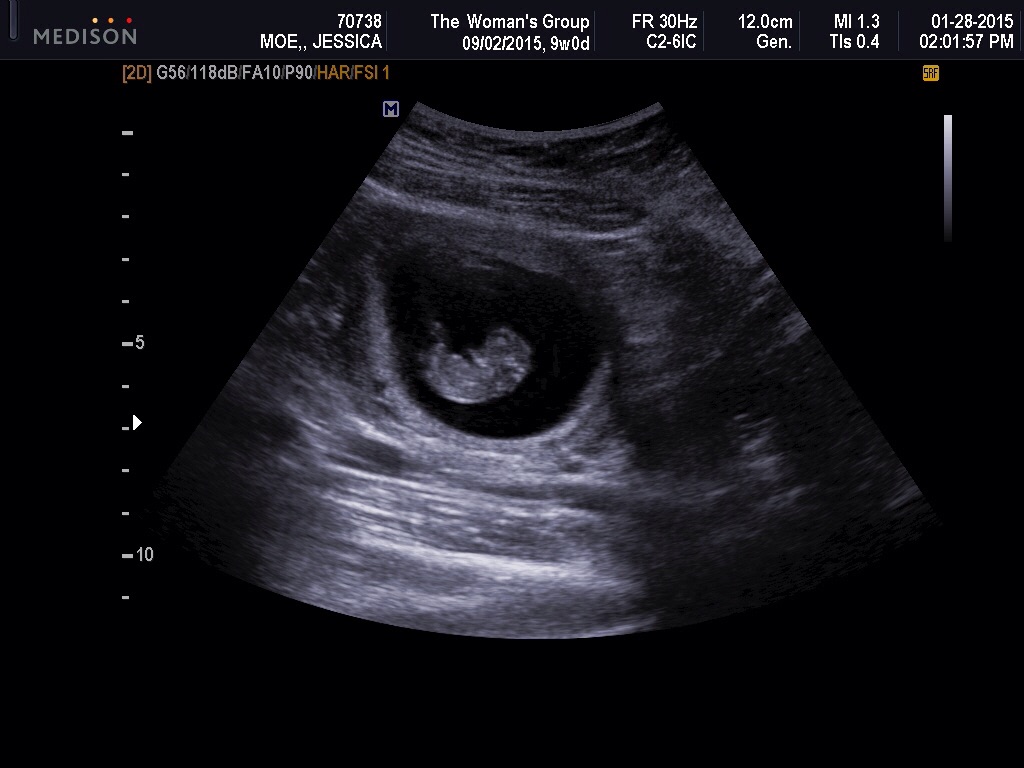

Second picture is 8 weeks 1 day also transvaginal